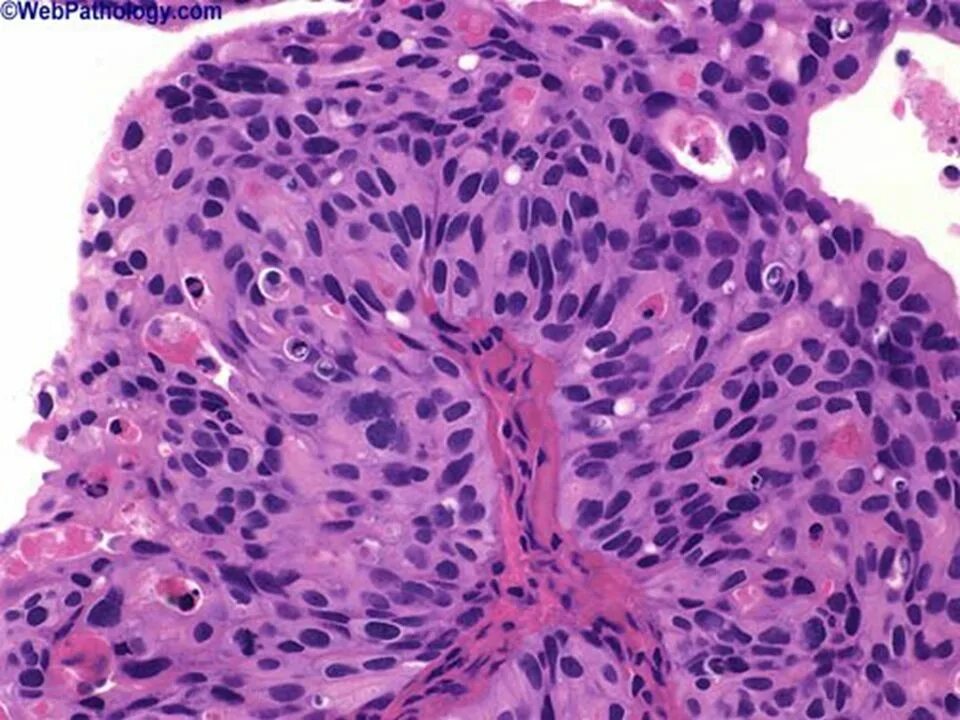

Выраженная атипия